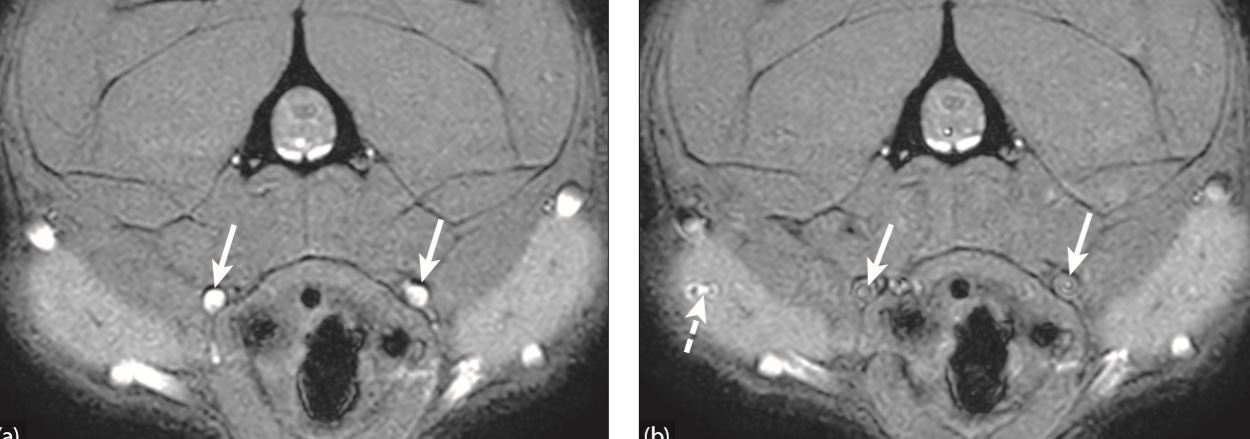

What artifact is this?

A

Motion/Phase mismapping

CSF flow artifact causing a pseudolesion

What is this artifact?

Pulsatility artifact/ghosting